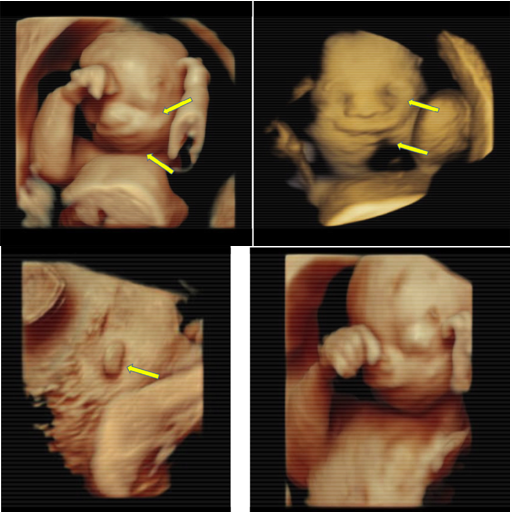

3D/4D Radiography

3D/4D imaging show fetal features that aid in the differential diagnosis of TCS. Unlike 2D imaging, 3D/4D can show micrognathia,palpebral downslanting, macrostomia, and microtia